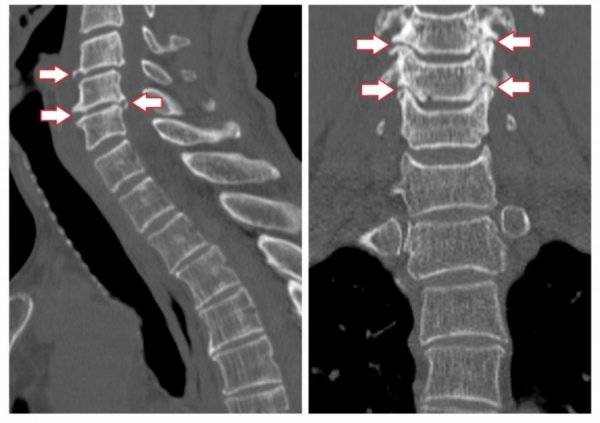

Подтвердить или опровергнуть диагноз позволяет рентген. Он определяет стадию развития заболевания и причину его возникновения. Более информативными методиками считается МРТ или КТ, но их назначают в отдельных случаях для получения развернутой картины состояния пациента.

Диагностировать клиновидное смещение можно с помощью рентгенографии поврежденного отдела в боковой и прямой задней проекции. На ранних стадиях лучше всего изменения зафиксировать при помощи томографии. Это дает возможность диагностировать трещину позвонка, грыжу, изменения в губчатом теле позвонка, остеопорозные изменения.